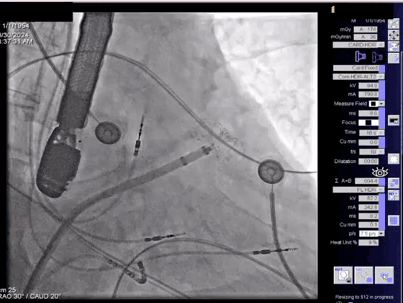

▲顺利展开封堵盘

接着保持钢缆不动,退鞘展开封堵盘,封堵盘密封形态良好,牵拉测试稳定,同时不影响毗邻结构。